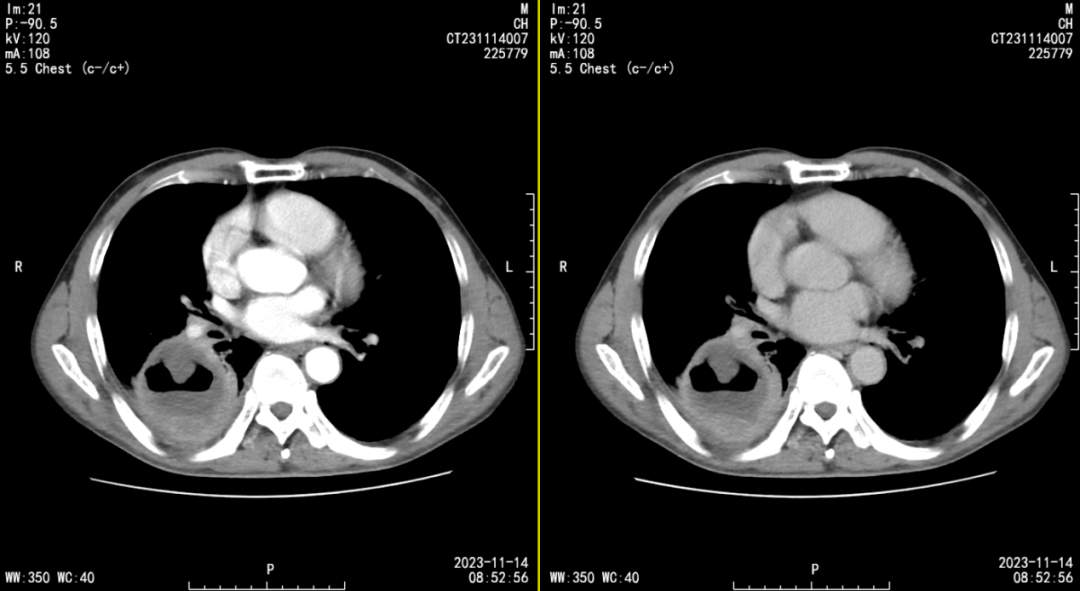

血源性多发性肺脓肿

图片尺寸823x516